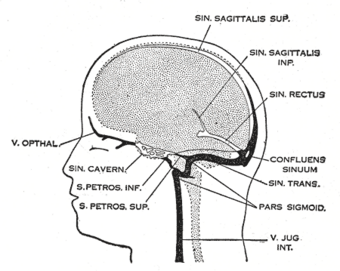

Gray488.png

Dural veins

Dural venous sinuses bordered by hard meninges (shown in blue) direct blood outflow from cerebral veins to the internal jugular vein at the base of skull

The veins of the brain, both the superficial veins and the deep venous system, empty into the dural venous sinuses, which carry blood back to the jugular vein and thence to the heart. In cerebral venous thrombosis, blood clots usually form both in the veins of the brain and the venous sinuses. The thrombosis of the veins themselves causes venous infarction (damage to brain tissue due to a congested and therefore insufficient blood supply). This results in cerebral edema (both vasogenic and cytotoxic edema), and leads to small petechial haemorrhages that may merge into large haematomas. Thrombosis of the sinuses is the main mechanism behind the increase in intracranial pressure due to decreased resorption of cerebrospinal fluid (CSF). The condition does not typically lead to hydrocephalus, however, because there is no difference in pressure between various parts of the brain.[3] However, those who have deep cerebral venous sinus thrombosis or oedema at basal ganglia are more prone to hydrocephalus development.[13]